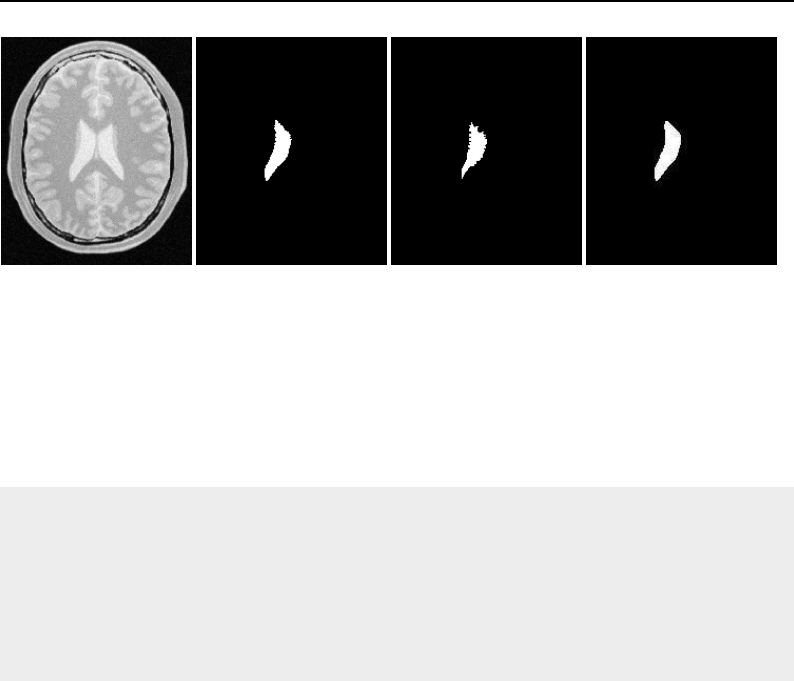

The National Library of Medicine Insight Segmentation and Registration Toolkit, shortened as the

Insight Toolkit (ITK), is an open-source software toolkit for performing registration and segmenta-

tion. Segmentation is the process of identifying and classifying data found in a digitally sampled

representation. Typically the sampled representation is an image acquired from such medical instru-

mentation as CT or MRI scanners. Registration is the task of aligning or developing correspondences

between data. For example, in the medical environment, a CT scan may be aligned with a MRI scan

in order to combine the information contained in both.